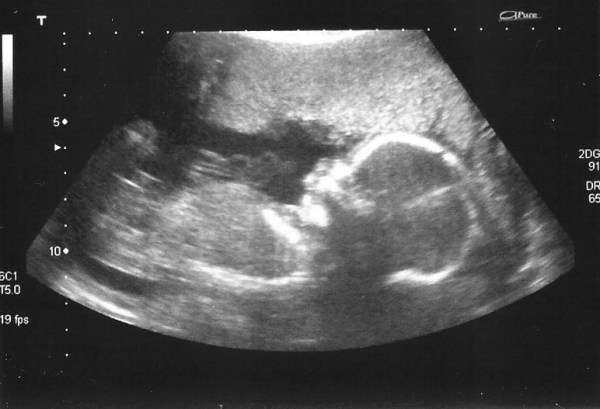

Today I went for my anomaly scan. I was half dreading it, half incredibly excited. I was counting down the time until I got to see little Shrimp on the screen again, but at the same time I was terrified about what they may find.

The scan wasn’t until the afternoon, which was probably good as I take ages to wake up properly in the morning nowadays, but when I realised I only had an hour to get ready I realised how quickly it had crept up on me. I booked it 2 months ago, and it had seemed forever away then, even a week to go seemed ages, but suddenly it was here and I was so not ready!

We were the first appointments after lunch, I chose them because I figured they couldn’t start to run behind so soon, SURELY! On the whole I was right, however they didn’t open reception until it was time for my appointment and the two people before me both took FOREVER, but after I had booked in we didn’t have long to wait until I was called in for my scan. She checked at the beginning if we would like a photo and whether or not we wanted to find out gender. We answered yes to both.

She started at the head, showing us the nose and eyes and lip and then she made her way down the body, looking at the skull circumference and measuring bits within the brain, checking the heart was ok, both kidneys were there, stomach, which she noted was full, and baby had clearly just had a drink, measuring the abdominal circumference, checking both legs were there and measuring the femur length. She then checked the spine and I think she could tell we were waiting with bated breath as she quickly reassured us everything was ok.

She then went inbetween the legs and quickly and very definitively told us it was a boy, pointing out the penis and scrotum! With both of us grinning like loons she checked a few other bits, took some lovely snap shots and sent us back to wait in the waiting room.

As soon as we got into the waiting room we were both instantly on our phones texting friends and family to let them know everything was ok and that we were having a little boy. We had decided on our boy name back at the beginning of our last pregnancy, so there was no doubt that he was going to be called Jackson Theo.